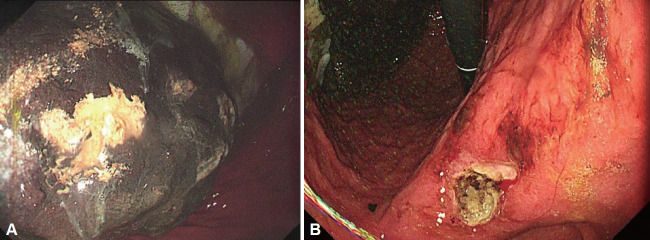

牛黄是一种难以消化的物质,可引起胃肠道并发症,如阻塞和穿孔。我们报告的情况下,60岁的男子与2型糖尿病和十二指肠溃疡手术史。患者出现大量胃植粪,引起持续性消化不良和胃脘痛。胃镜检查证实胃角处有10厘米的植物性牛黄和1.5厘米的活动性溃疡。为了软化牛黄,病人服用了可口可乐和纤维素酶。这种治疗方法显著降低了牛黄的硬度,使其能够成功地使用常规设备进行内窥镜碎裂。在三次内窥镜检查中,牛黄被粉碎成小于1厘米的碎片并被取出;此后,胃溃疡完全愈合。本病例说明了将可口可乐和纤维素酶的作用与内窥镜方法结合治疗大牛黄的有效性,为社区卫生保健机构提供了一种手术方法的替代方法。

Bezoars are indigestible masses that can cause gastrointestinal complications such as obstructions and perforations. We report the case of a 60-year-old man with a history of type 2 diabetes mellitus and duodenal ulcer surgery. The patient developed a large gastric phytobezoar that caused persistent dyspepsia and epigastric pain. Upper endoscopy confirmed a 10-cm phytobezoar and a 1.5-cm active ulcer at the gastric angle. To soften the bezoar, Coca-Cola and cellulase were administered to the patient. This treatment significantly reduced the bezoar's hardness, permitting its successful endoscopic fragmentation using conventional devices. Over three endoscopic sessions, the bezoar was fragmented into pieces smaller than 1 cm and removed; thereafter, the gastric ulcer healed completely. This case illustrates the effectiveness of combining the actions of Coca-Cola and cellulase with endoscopic methods to treat large bezoars, providing an alternative to surgical approaches in community healthcare settings.